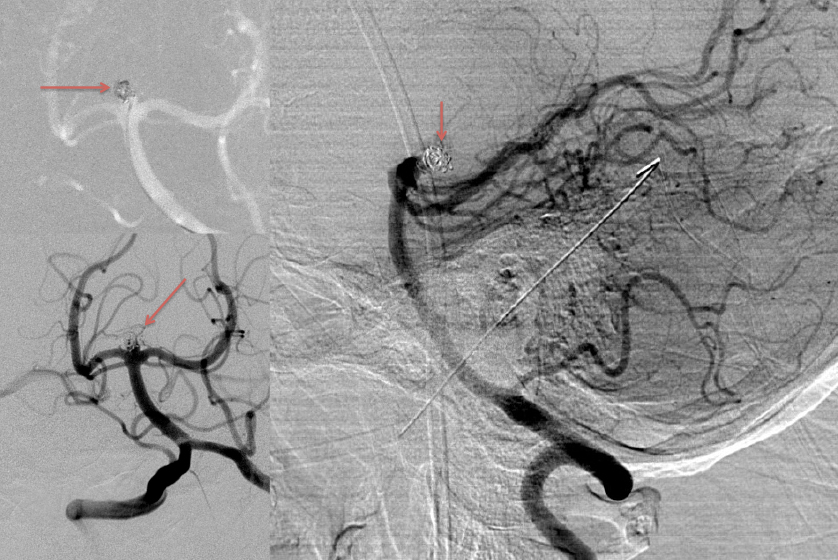

A man in his 40’s experienced an acute onset of a moderate headache. Over the next 3 days, his family noticed increased lethargy, decreased appetite, and gait imbalance, which prompted them to bring him to the ED for evaluation. Initial CT scan of the brain confirmed diffuse subarachnoid hemorrhage with hydrocephalous, which required emergent EndoVentricular Drainage for a progressive diminished level of consciousness, WFNS Grade 3-4 (Figure 1).

Urgent Cerebral Angiography confirmed a 5 mm posteriorly projecting aneurysm of the Basilar Artery Apex (Figure 2 A, B). Based on the location, morphology, and posterior projection, we decided to proceed to coil embolization of this high-risk aneurysm to prevent catastrophic re-bleeding and afford us the opportunity to maximize critical care for this patient during his hospital course. In this aneurysm, the dome-neck ratio was favorable from primary coiling, which was successfully performed resulting in near-complete embolization of the aneurysm (Figure 3 A, B). After 2 weeks of continued critical current l, endovascular, and neurosurgical care for complications of subarachnoid hemorrhage, including vasospasm and hydrocephalous, he was able to make a complete recovery and ultimately discharged home to complete his recovery, having regained all neurologic functions and activities of independent daily living and planning a return to work as an executive professional in the near future.

Figure 3: A) Initial Coil placement in Aneurysm dome B) Final AP and C) Lateral DSA demonstrating near complete obliteration of the ruptured aneurysm